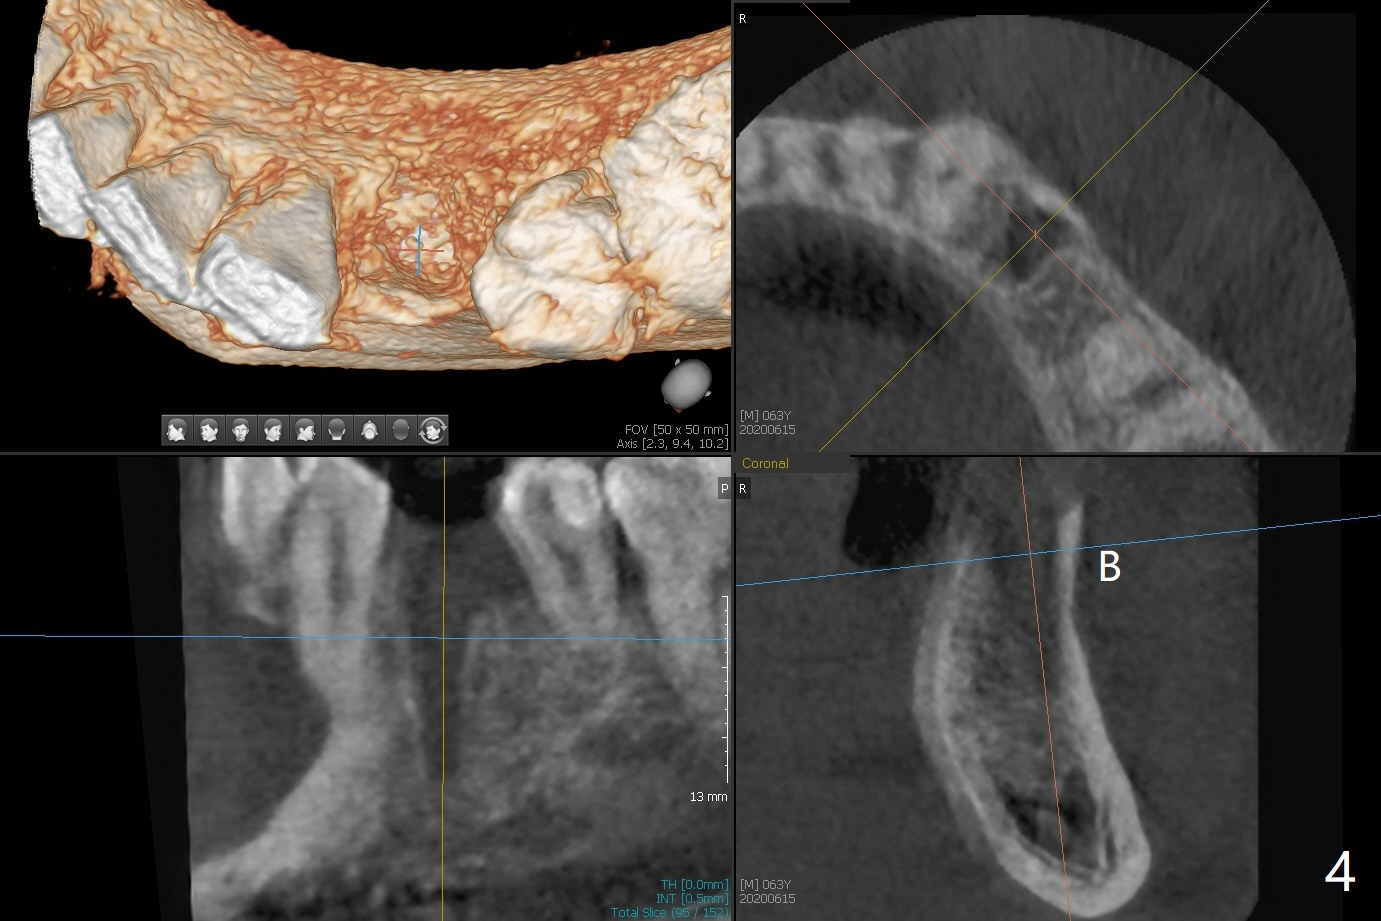

Three months post guide fabrication (coronavirus outbreak), the patient with loose post/crown returns for #21 extraction and immediate implant with guide (Fig.1 (*: post space)). In fact the root stump is flattened with diamond bur and 9 mm bone trimmer with guide before point drill. When the osteotomy finishes with 3.5x13 mm drill (under drilling with 10.5 mm offset), it has deviated buccal (Fig.2, 3,4); the outline of the bone trimmer mark is labeled by arrowheads in Fig.2. It appears that the center of the bone trimmer is dictated by that of the post space, as compared to Fig.1 *). When the root is removed except buccal shield (assuming that the deviation was due to the uneven surface of the root stump), the osteotomy is redone with guide, but remains buccal. Finally with buccal shield removal, a new lingual osteotomy is created free hand for a 4.5x11 mm implant (Fig.5) with 2-3 mm buccal gap for bone graft (Fig.6 * (literally)). In brief, bone trimmer also deviates according to resistance, basically irrelevant to the guide sleeve. The immediate provisional is intentionally removed 5 days postop to check whether a piece of gauze is retained in the socket as a gingival retraction cord for temporary crown fabrication; the buccal gap is kept with bone graft (Fig.7 *). No foreign body is in place. The margin of the abutment seems quite subgingival (Fig.8 *), but re-trimmed and polished provisional looks harmonious with the surrounding gingiva and the opposing dentition (Fig.9,10). The patient returns for prophy 2 months postop; the immediate provisional is removed for trimming and polishing. The bone graft seems to be integrated into a part of the gingiva (Fig.11 >). The abutment cuff appears to be too short.